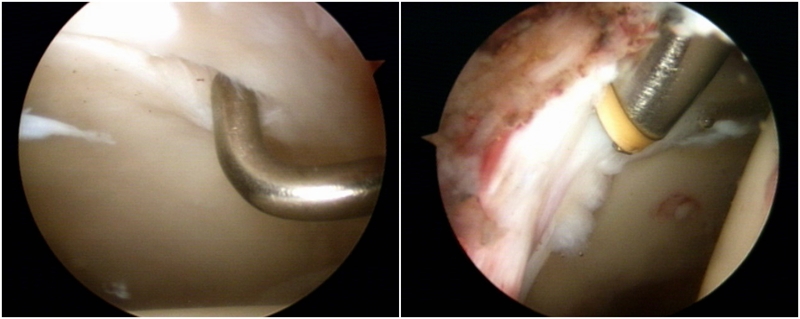

图4 髋关节镜术中图片,可见明显盂唇撕裂伴充血

图9 Cam型撞击,通过磨钻磨除

2.盂唇损伤的治疗:盂唇损伤广泛存在于髋关节撞击综合征中。对于存在修复条件的盂唇损伤,目前推荐行盂唇修复术;而对于盂唇严重磨损无法修复或横断的情况,则可考虑行盂唇清理、盂唇部分修复或盂唇重建术。手术原则是对损伤的髋臼盂唇尽量予以缝合修复,恢复髋臼盂唇的解剖结构,从而恢复髋臼盂唇的功能,避免由于髋臼盂唇缺损造成的髋关节退变。